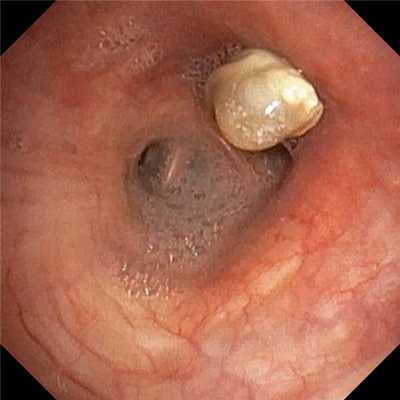

Инвертированное, отечное устье червеобразного отростка в просвет слепой кишки при аппендикулярном инфильтрате